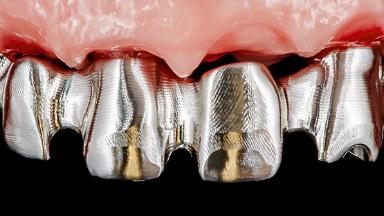

Rehabilitating an Edentulous Maxilla with a Fixed Dental Prosthesis Following Provisional Immediate Loading

This case features the flapless computer-guided placement of 7 bone-level implants, distributed to provide maximal support for the prosthetic framework. A rigid one-piece metallic framework was utilized as an interim restoration to reduce the risk of fracture associated with this prosthetic design. As part of the clinical examination, the SAC Assessment Tool was used, resulting in a surgical and restorative risk classification as “complex”.

Prosthesis Type FDP

Loading Protocol Immediate